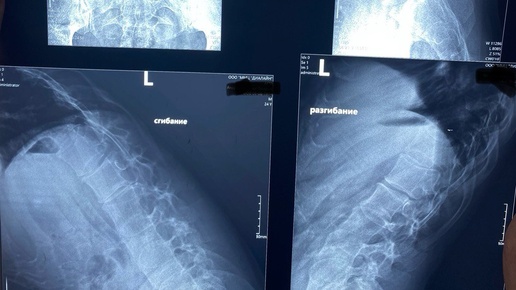

Сколиоз — это боковое искривление позвоночника, которое может приводить к деформации как самого позвоночного столба, так и связанным с ним органам. Это заболевание может развиваться в любом возрасте, но особенно часто проявляется в детском и подростковом периодах. Причины сколиоза могут варьироваться: Симптомы сколиоза могут различаться в зависимости от возраста пациента: Диагностика сколиоза начинается с клинического осмотра врача, который обращает внимание на симметрию тела и осанку пациента...

Согласно исследованием, если врачи сосредотачиваются на лечении основной причины сколиоза, взрослые пациенты испытывают меньше боли, а их состояние улучшается. Поэтому болезнь не стоит запускать, ведь есть шанс восстановить качество жизни. Типы сколиоза у взрослых Сколиоз - это аномальное искривление позвоночника. При этом заболевании позвоночник вращается и изгибается из стороны в сторону. Такие отклонения могут быть как совсем незначительными (10 градусов), так и довольно серьезными, например, 100 градусов и более...